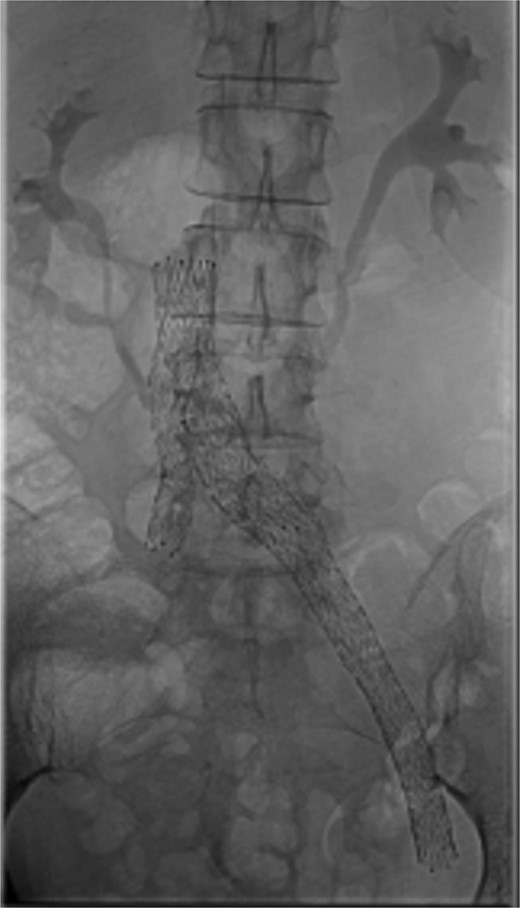

Bilateral popliteal venous access was obtained. Venography confirmed patency of the IVC, left iliac vein, and stents. Thrombolysis of the right lower limb was performed with AngioJet Zelante and 10 mg of alteplase (lower dose to minimize hematoma complications). The IVC filter was then removed to allow extension of a Venovo 12 × 80 mm stent positioned in the right iliac vein, and a Venovo 14 × 80 mm superior extension on the left. Both stents were deployed simultaneously in a ‘kissing’ configuration and post-dilatated with Mustang 12 × 100 mm balloons (Fig. 4). The completion venogram showed smooth contrast flow in both limbs with the disappearance of collateral veins.

This case highlights valuable lessons about iliac vein stenting near the caval influence. ‘Kissing’ venous stents are safe, feasible, and should strongly be considered upfront to avoid repeat contralateral procedures. Intra-venous ultrasound (IVUS) has been recommended to guide sizing. It also helps to objectively compare the pre- and post-treatment effects [9]. In our case, IVUS was not available due to the emergency procedures being performed after hours.